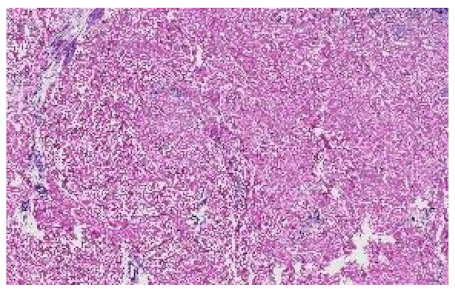

The preprocessing stage began with 66 WSI scans; we digitally cropped one region of interest (ROI) of size 1440 × 904 pixels for each tissue type in each slide. This resulted in three sets of images of 66 ROIs each, one set for the kidney, one for the skin, and one for the colon tissue. Cropping was used to minimize the presence of the non-tissue-related background, such as dust, hair, fibers, and other artifacts from previous preprocessing steps. The selected region coordinates were approximately the same within each tissue type. Each ROI was localized to cover an approximately sufficient area in each tissue type. Figure 3 shows samples of such ROIs for each tissue type amongst nine randomly chosen laboratories (three laboratories per tissue type).

Figure 3.

For illustration purposes, three ROIs from three laboratories per tissue type (column-wise). The first column is skin, the second column is kidney, and the last column is colon.